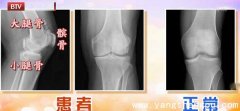

我们膝关节的中间(大腿骨与小腿骨之间)有一条0.5厘米的缝,这个缝隙里面实际上是我们的软骨和半月板,起到了润滑和减震的作用。在X光线下软骨和半月板被X线照透了,所以在X...